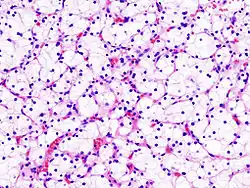

Microscopically, CCRCCs are graded by the ISUP/WHO as follows:[1][2]

- Grade 3: Clearly visible nucleoli at magnification of 100 times

Grade 3: Arrows point at a clearly visible nucleolus.